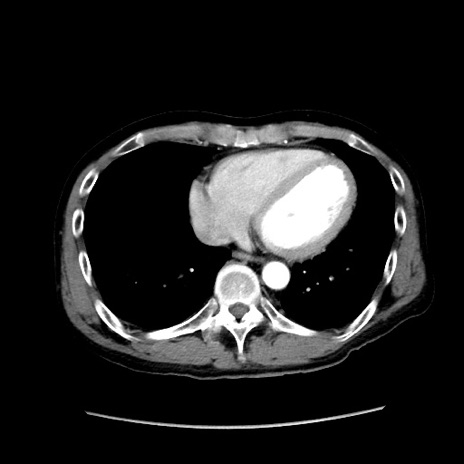

冠状断像